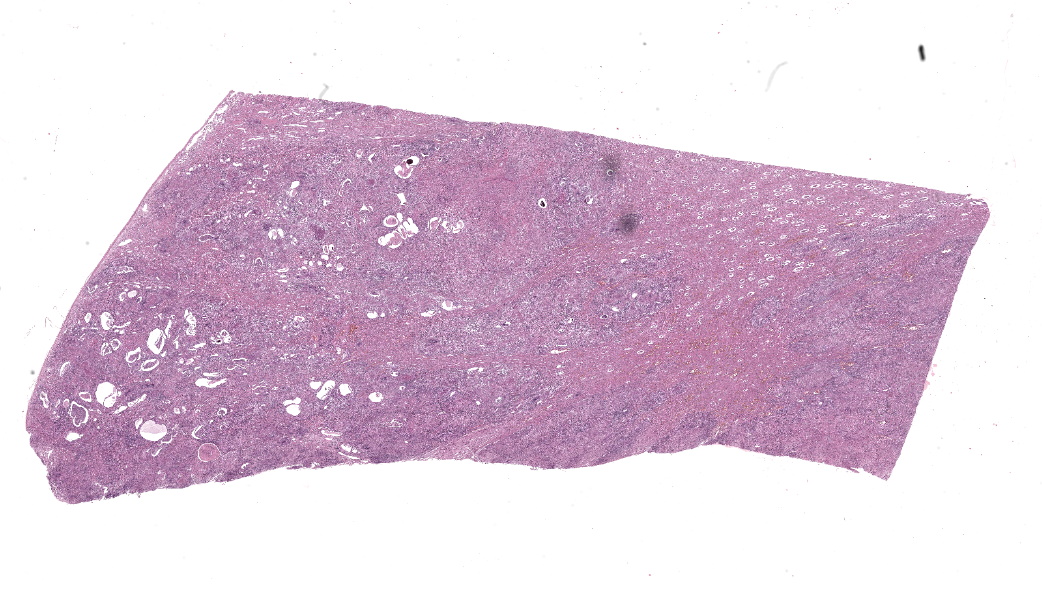

Gross Pathology:

The kidneys had multifocal nodules, ranging from 2 to 15 cm in diameter, elevated, white-yellowish in the center, red on the edges, and firm. In the right kidney the lesion replaced, approximately, fifty percent of the renal parenchyma, whereas in the left kidney there were multiple nodules ranging from 1 to 3 cm in diameter. Renal and internal iliac lymph nodes were moderately enlarged and firm, with undefined cortico-medullary distinction. Meninges and brain parenchyma were moderately hyperemic.

Microscopic Description:

Kidneys: Multifocal to coalescent areas of loss of normal parenchyma with replacement by severe lymphohistioplasmocytic inflammatory infiltrate, with epithelioid macrophages, multinucleated giant cells, and large numbers of intralesional nematodes. Parasites were elongated, with aproximately 80 to 90 μm long (most of them fragmented), cylindrical, with sharp ends, covered by smooth cuticle, platimiarian musculature and an evident elongated and central rhabditiform esophagus, occupying the initial third of the body (morphology consistent with Halicephalobus gingivalis). Associated with these lesions there were also fibroplasia, necrosis, vasculitis and the remaining renal tubules were dilated and filled with macrophages, neutrophils, cellular debris, and numerous sections of H. gingivalis.

Contributor’s Morphologic Diagnoses:

Kidneys: multifocal to coalescent, severe, chronic, granulomatous nephritis associated to intralesional nematodes compatible with Halicephalobus gingivalis and multifocal, severe, vasculitis, horse.